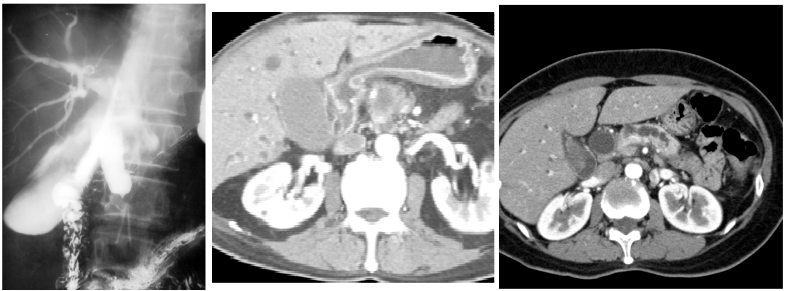

73.65歲林先生,近日來感覺疲倦、食慾減退、皮膚發黃。血液檢查肝功能異常、CA-199值升高。醫師為他做CT 檢查,影像如圖示。林先生最可能患了什麼病? (A)肝內膽管癌(intrahepatic cholangiocarcinoma) (B)肝細胞癌(hepatocellular carcinoma) (C)胃癌(gastric cancer) (D)胰臟頭癌(pancreatic head cancer)